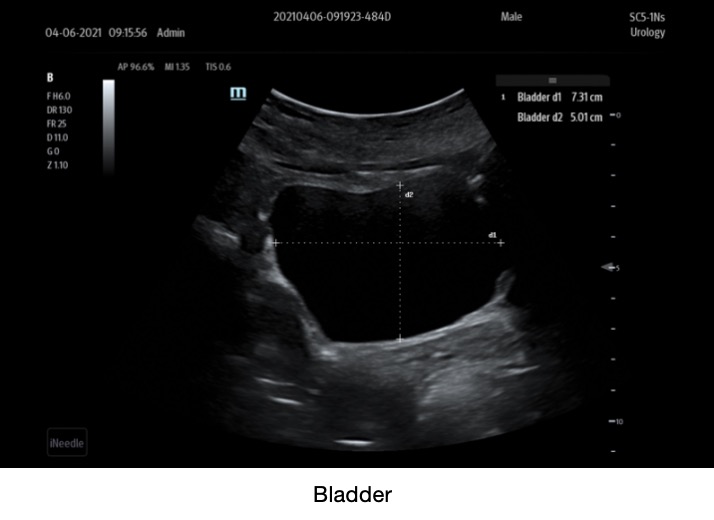

Clinical Images